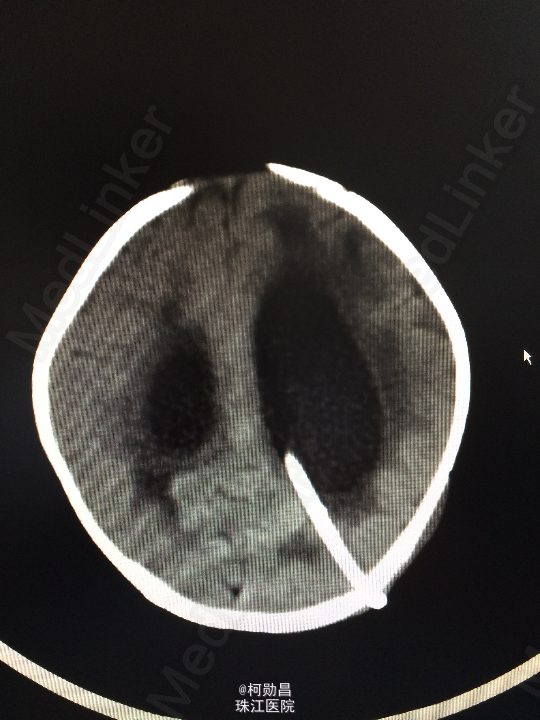

查体:神志不清,四肢肌力增高 辅助检查:头颅CT提示脑积水并脑脊液外渗,幕上脑室扩张,右侧额颞叶硬膜下脑脊

诊断:化脓性脑膜炎伴脑积水 处理:予内科抗感染治疗,后行脑室腹腔引流术。